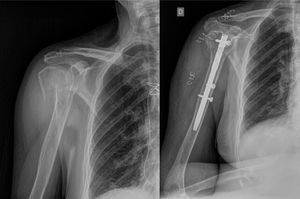

Inasmuch as the type of hip fracture is concerned, the distribution of intracapsular fractures among the people in the FCMS group relative to the group of cases of isolated hip fracture was 28.6% vs. 39.8%, while extracapsular fractures displayed a distribution of 71.4% vs. 60.2%, respectively (Fig. 1; Table 2).

Of the subjects with FCMS, 8.1% (5/63) underwent surgery to treat their upper limb fracture, while 91.9% (58/63) were managed conservatively (Fig. 2).

The hip fractures were classified as intra- or extracapsular fractures; in addition, the management of the hip fracture and the associated upper limb fracture was documented as conservative or surgical. All the subjects who had suffered an extracapsular fracture were treated with endomedullary nailing, while those with intracapsular fractures were treated according to the Garden I or II classification with conservative treatment or osteosynthesis using cannulated screws; Garden types III or IV fractures were surgically treated with hip arthroplasty.

The most common site of concomitant upper limb fracture was the distal radius, which was found in 31 people (49.2%), followed by the proximal humerus, which was detected in 20 cases (31.7%). Other less frequent fracture sites were the olecranon, clavicle, or distal humerus, accounting for 19.1% of the patients.

For the most part, concomitant fractures of the upper limb tend to involve fractures of the distal radius and of the proximal humerus.4,5,9,14,15 In our series, the results obtained are consistent with those of other studies in the literature: 81% of the upper extremity fractures occurred in the distal radius and proximal humerus.

The vast majority of the FCMS from our series were treated conservatively (91.9%) and had a negative impact on patient mortality and length of hospital stay, in line with other publications4,6,13,16–21; nevertheless, Buecking et al. treated FCMS surgically in a larger percentage of their subjects (56%) and their series reflected no increase in duration of hospitalisation (14 vs. 14 days, p=0.799) or mortality rate (9.5% vs. 5.9%, p=.003) in their cases of FCMS.17 Lee et al. observed no significant differences in mortality or hospital stay in people with concomitant upper extremity fractures of either the distal radius or proximal humerus, albeit they did observe better functional outcomes among individuals who suffered an associated fracture of the distal radius as opposed to the proximal humerus.22 Ganta et al. compared cases of concomitant proximal humerus fractures that underwent conservative vs. surgical treatment, and found no significant differences with respect to length of hospitalisation or destination at discharge. They indicate that a greater proportion of patients return to their former functional status; however, this difference has not reached the level of statistical significance (70% vs. 52%, p=.342).23 Therefore, one should contemplate the possibility that patients with a hip fracture and FCMS might benefit from surgical treatment of the upper limb injury, despite the fact that in other circumstances, this fracture would warrant conservative treatment.